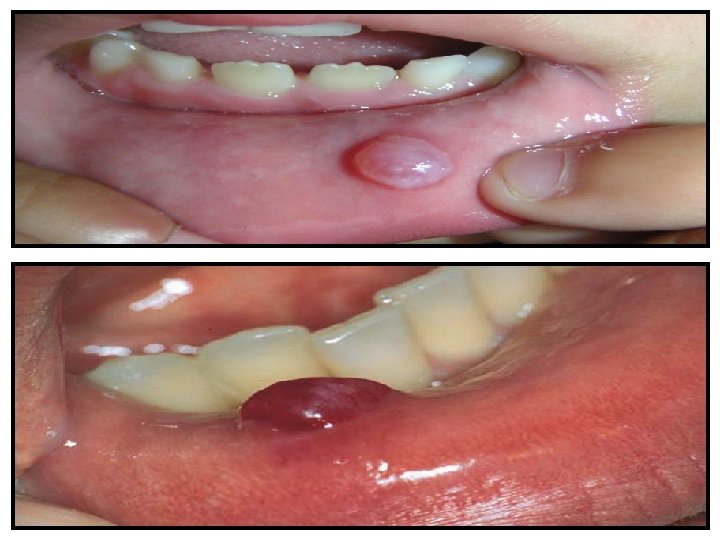

EXAMINATION OF THE RESPIRATORY SYSTEM Eruption cysts and mucoceles are not • uncommon in the first 6 months. Any caries should be noted. The teeth should be examined for a malocclusion. Natal teeth may be seen in the newborn period. A single central maxillary incisor can be associated with growth hormone deficiency. Maxillary hyperplasia may be seen with various forms of chronic anemia.

CLINICAL FEATURES These asymptomatic lesions are located along the angle of the mandible if arising from the first branchial cleft and the middle to lower third of the anterior border of the sternocleidomastoid in cases arising from the second branchial cleft. They may present after an upper respiratory infection as a painful mass. These lesions tend to drain internally, but communication with the epidermis can occur. Branchial cysts may become complicated by infection.